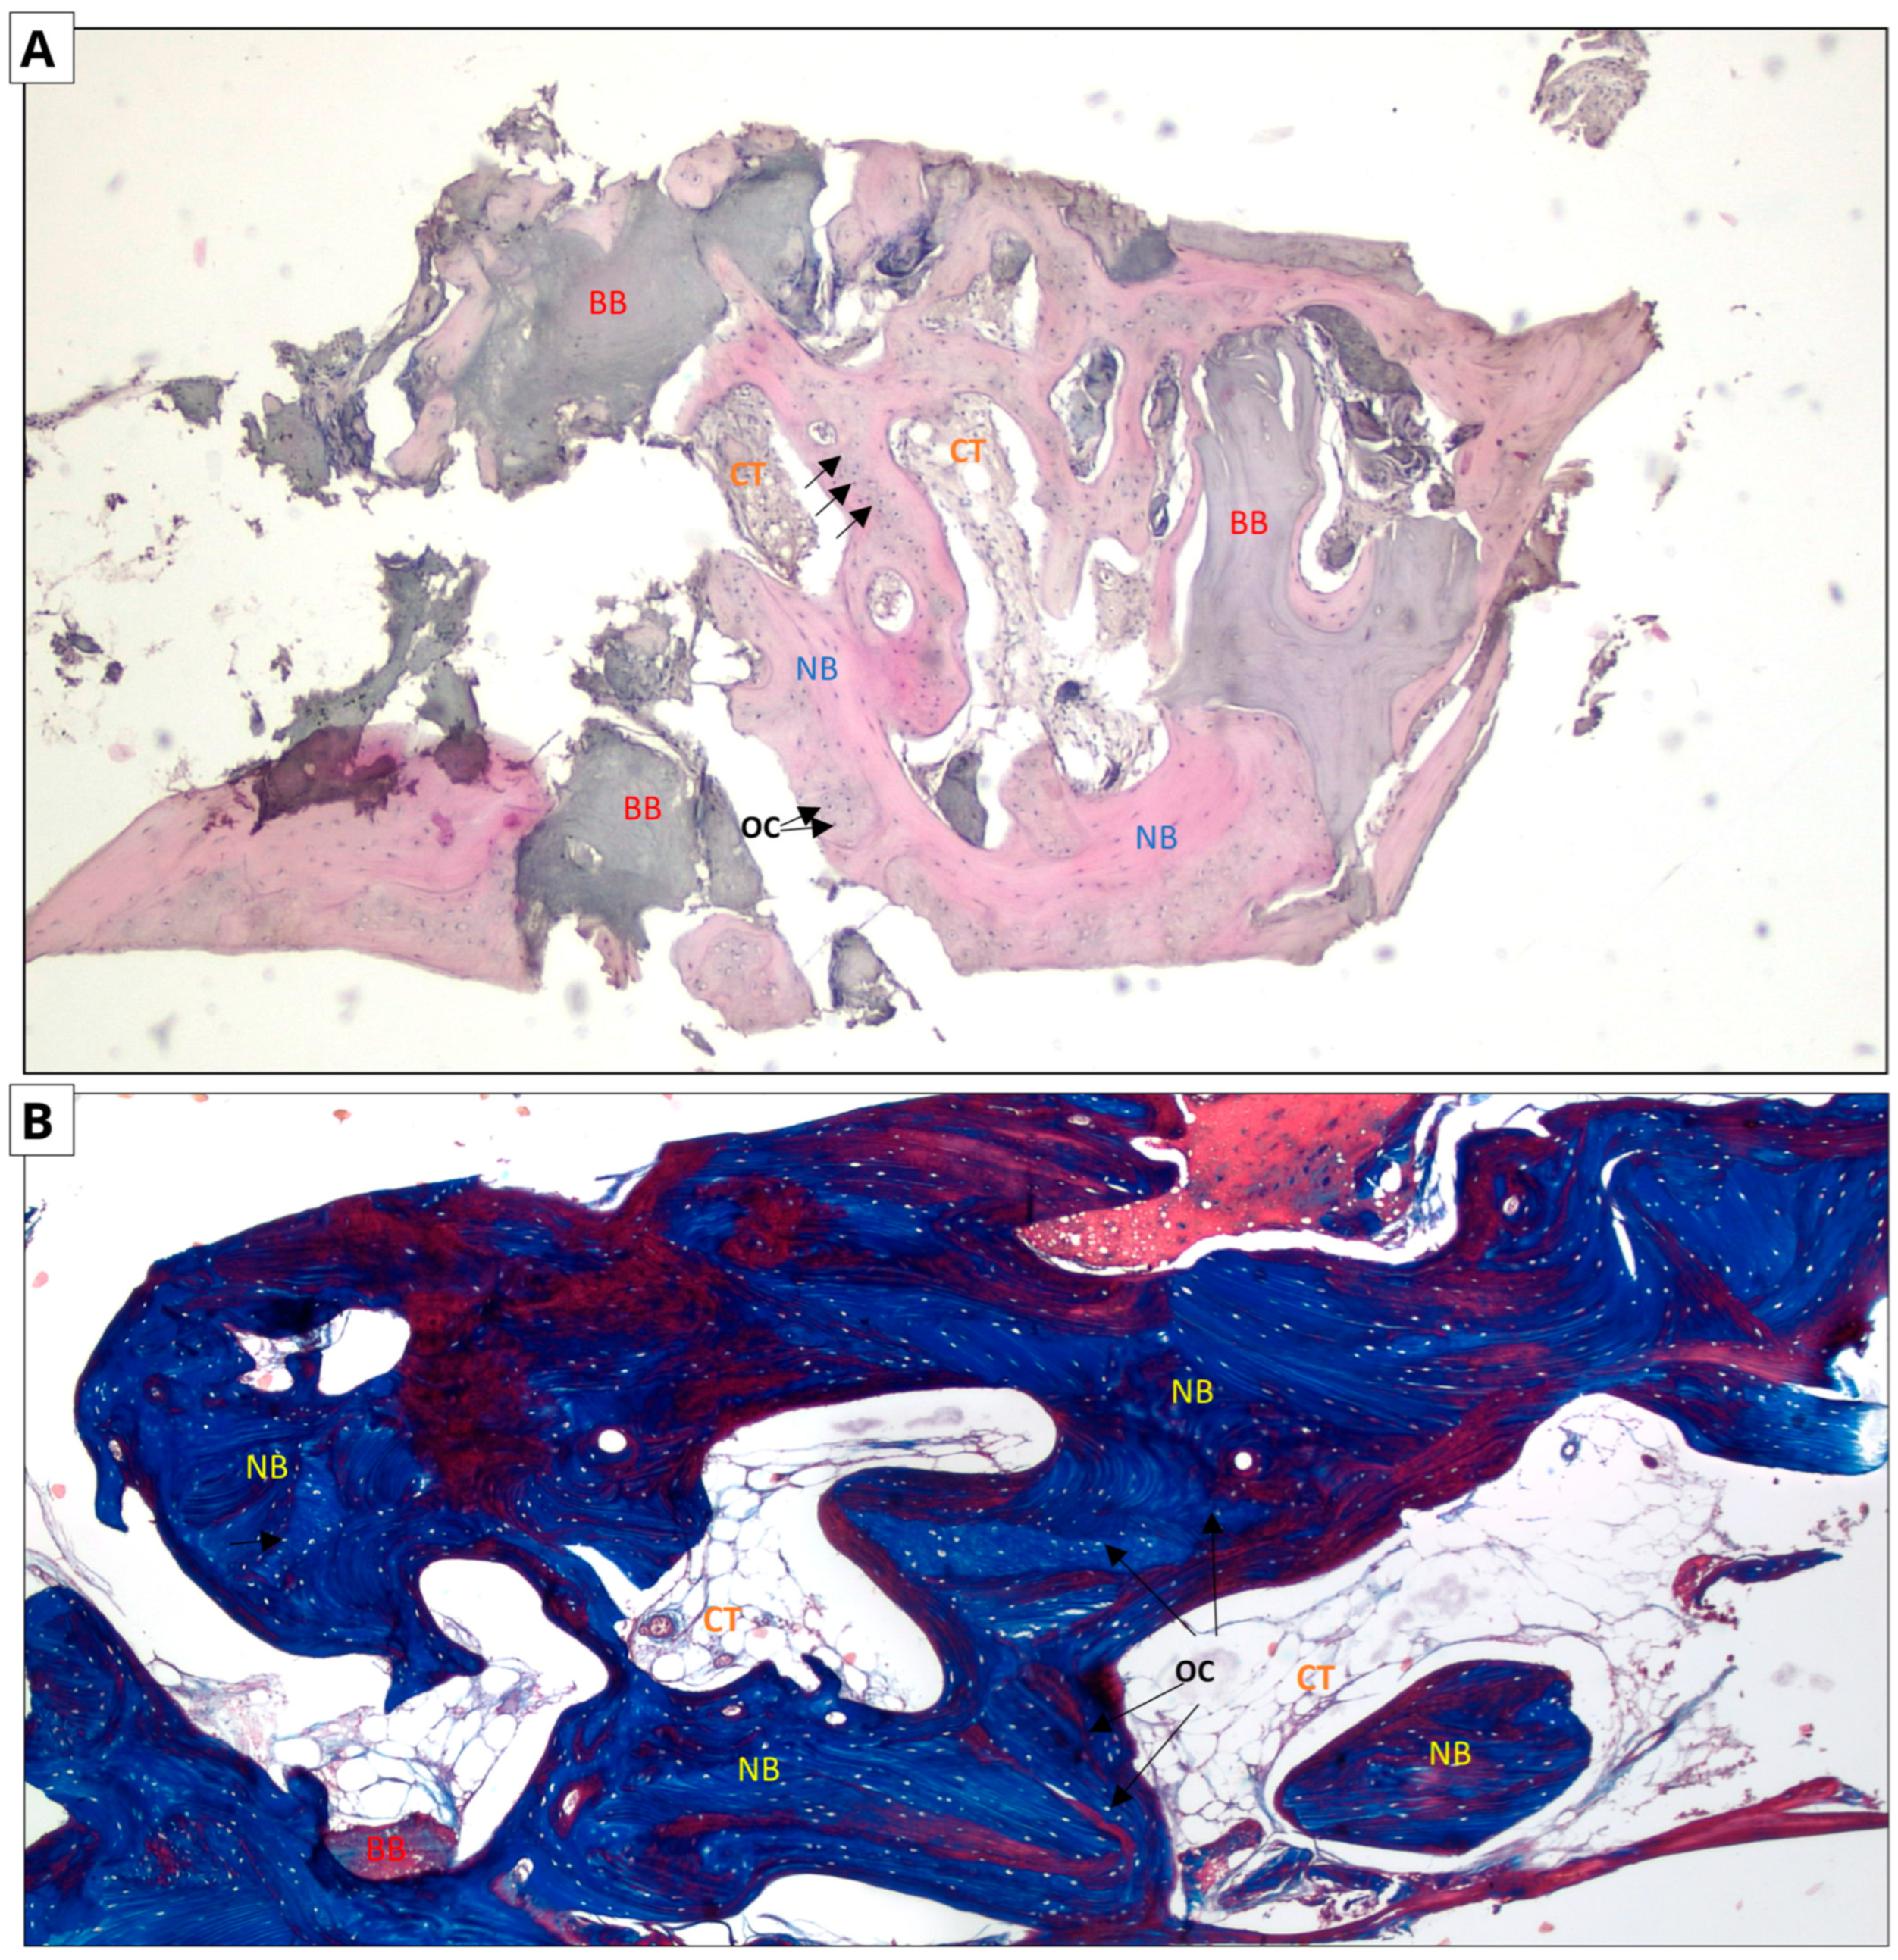

The following micrographs show specimens stained with hematoxylin and eosin and Masson’s trichrome with aniline blue (Figure 6 and Figure 7). In all five trepanobiopsies, taken from patients with xenografts, residual graft material particles were found in the slides. In the group of patients where the augmentation material was an allograft, residual graft particles were found in only one trepanobiopsy.

Figure 6.

Allograft group. Two-dimensional (2D) reconstruction of the bone sample at ×40 magnification. (A) Hematoxylin and eosin staining; (B) Masson’s trichrome staining. Woven bone stained blue and lamellar bone stained red. Residual allograft particles (BB) surrounded by newly formed bone tissue (NB) containing osteocytes (OCs, arrows). Connective tissue (CT) consisting of fibroblasts and adipocytes.

In the case of hematoxylin and eosin staining, the presence of new bone tissue in direct contact with the augmentation material was observed in both samples. A similar structure to the connective tissue, with numerous fibroblasts and fewer adipocytes, was also visible, which may correspond to bone marrow. No inflammatory cells were observed. The above-mentioned observations indicate the biocompatibility of both materials.

In the case of Masson staining, some differences were observed. The samples from the xenograft group included areas of bone with an irregular arrangement of collagen fibers, stained blue, which may correspond to woven bone. In the samples from the allograft group, areas that may correspond to woven bone were also observed. In addition, there were noticeable areas of bone with a regular arrangement of collagen fibers, stained red, which may correspond to lamellar bone, indicating the completion of the bone remodeling process.